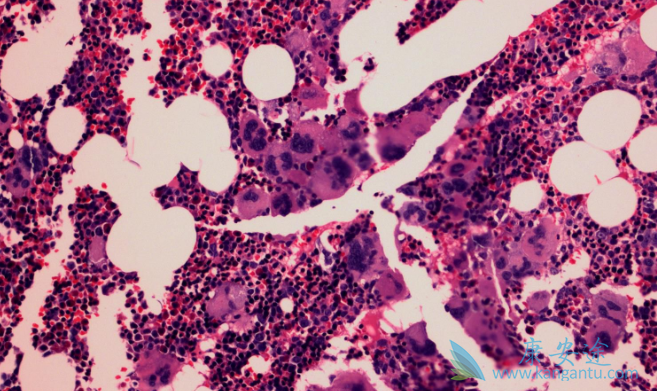

骨髓纤维化(MF)是一种骨髓造血干细胞异常克隆所致的、以骨髓中出现网状纤维和胶原纤维为特征的血液恶性肿瘤,包括PMF,以及继发于PV和ET的PPV-MF和PET-MF。在芦可替尼出现以前,MF没有有效治疗药物,只能等待疾病进展进而对症处理。芦可替尼是一种强效JAK1/2抑制剂,可针对MF发病机制,下调JAK-STAT信号通路,达到靶向治疗骨髓纤维化的目的。那芦可替尼治疗骨髓纤维化有什么优势呢?

(3)芦可替尼可以显著延长骨髓纤维化患者生存。最新公布的COMFORT-I/II 5年汇集分析显示芦可替尼可以降低MF患者死亡风险30%。如排除交叉入组干扰,芦可替尼的优势更加明显,可降低死亡风险65%。此外,有研究提示尽早、足剂量用药可以为患者带来更大生存获益。(4)持久改善及稳定骨髓纤维化。芦可替尼长期治疗可阻止甚至逆转骨髓纤维化进展。